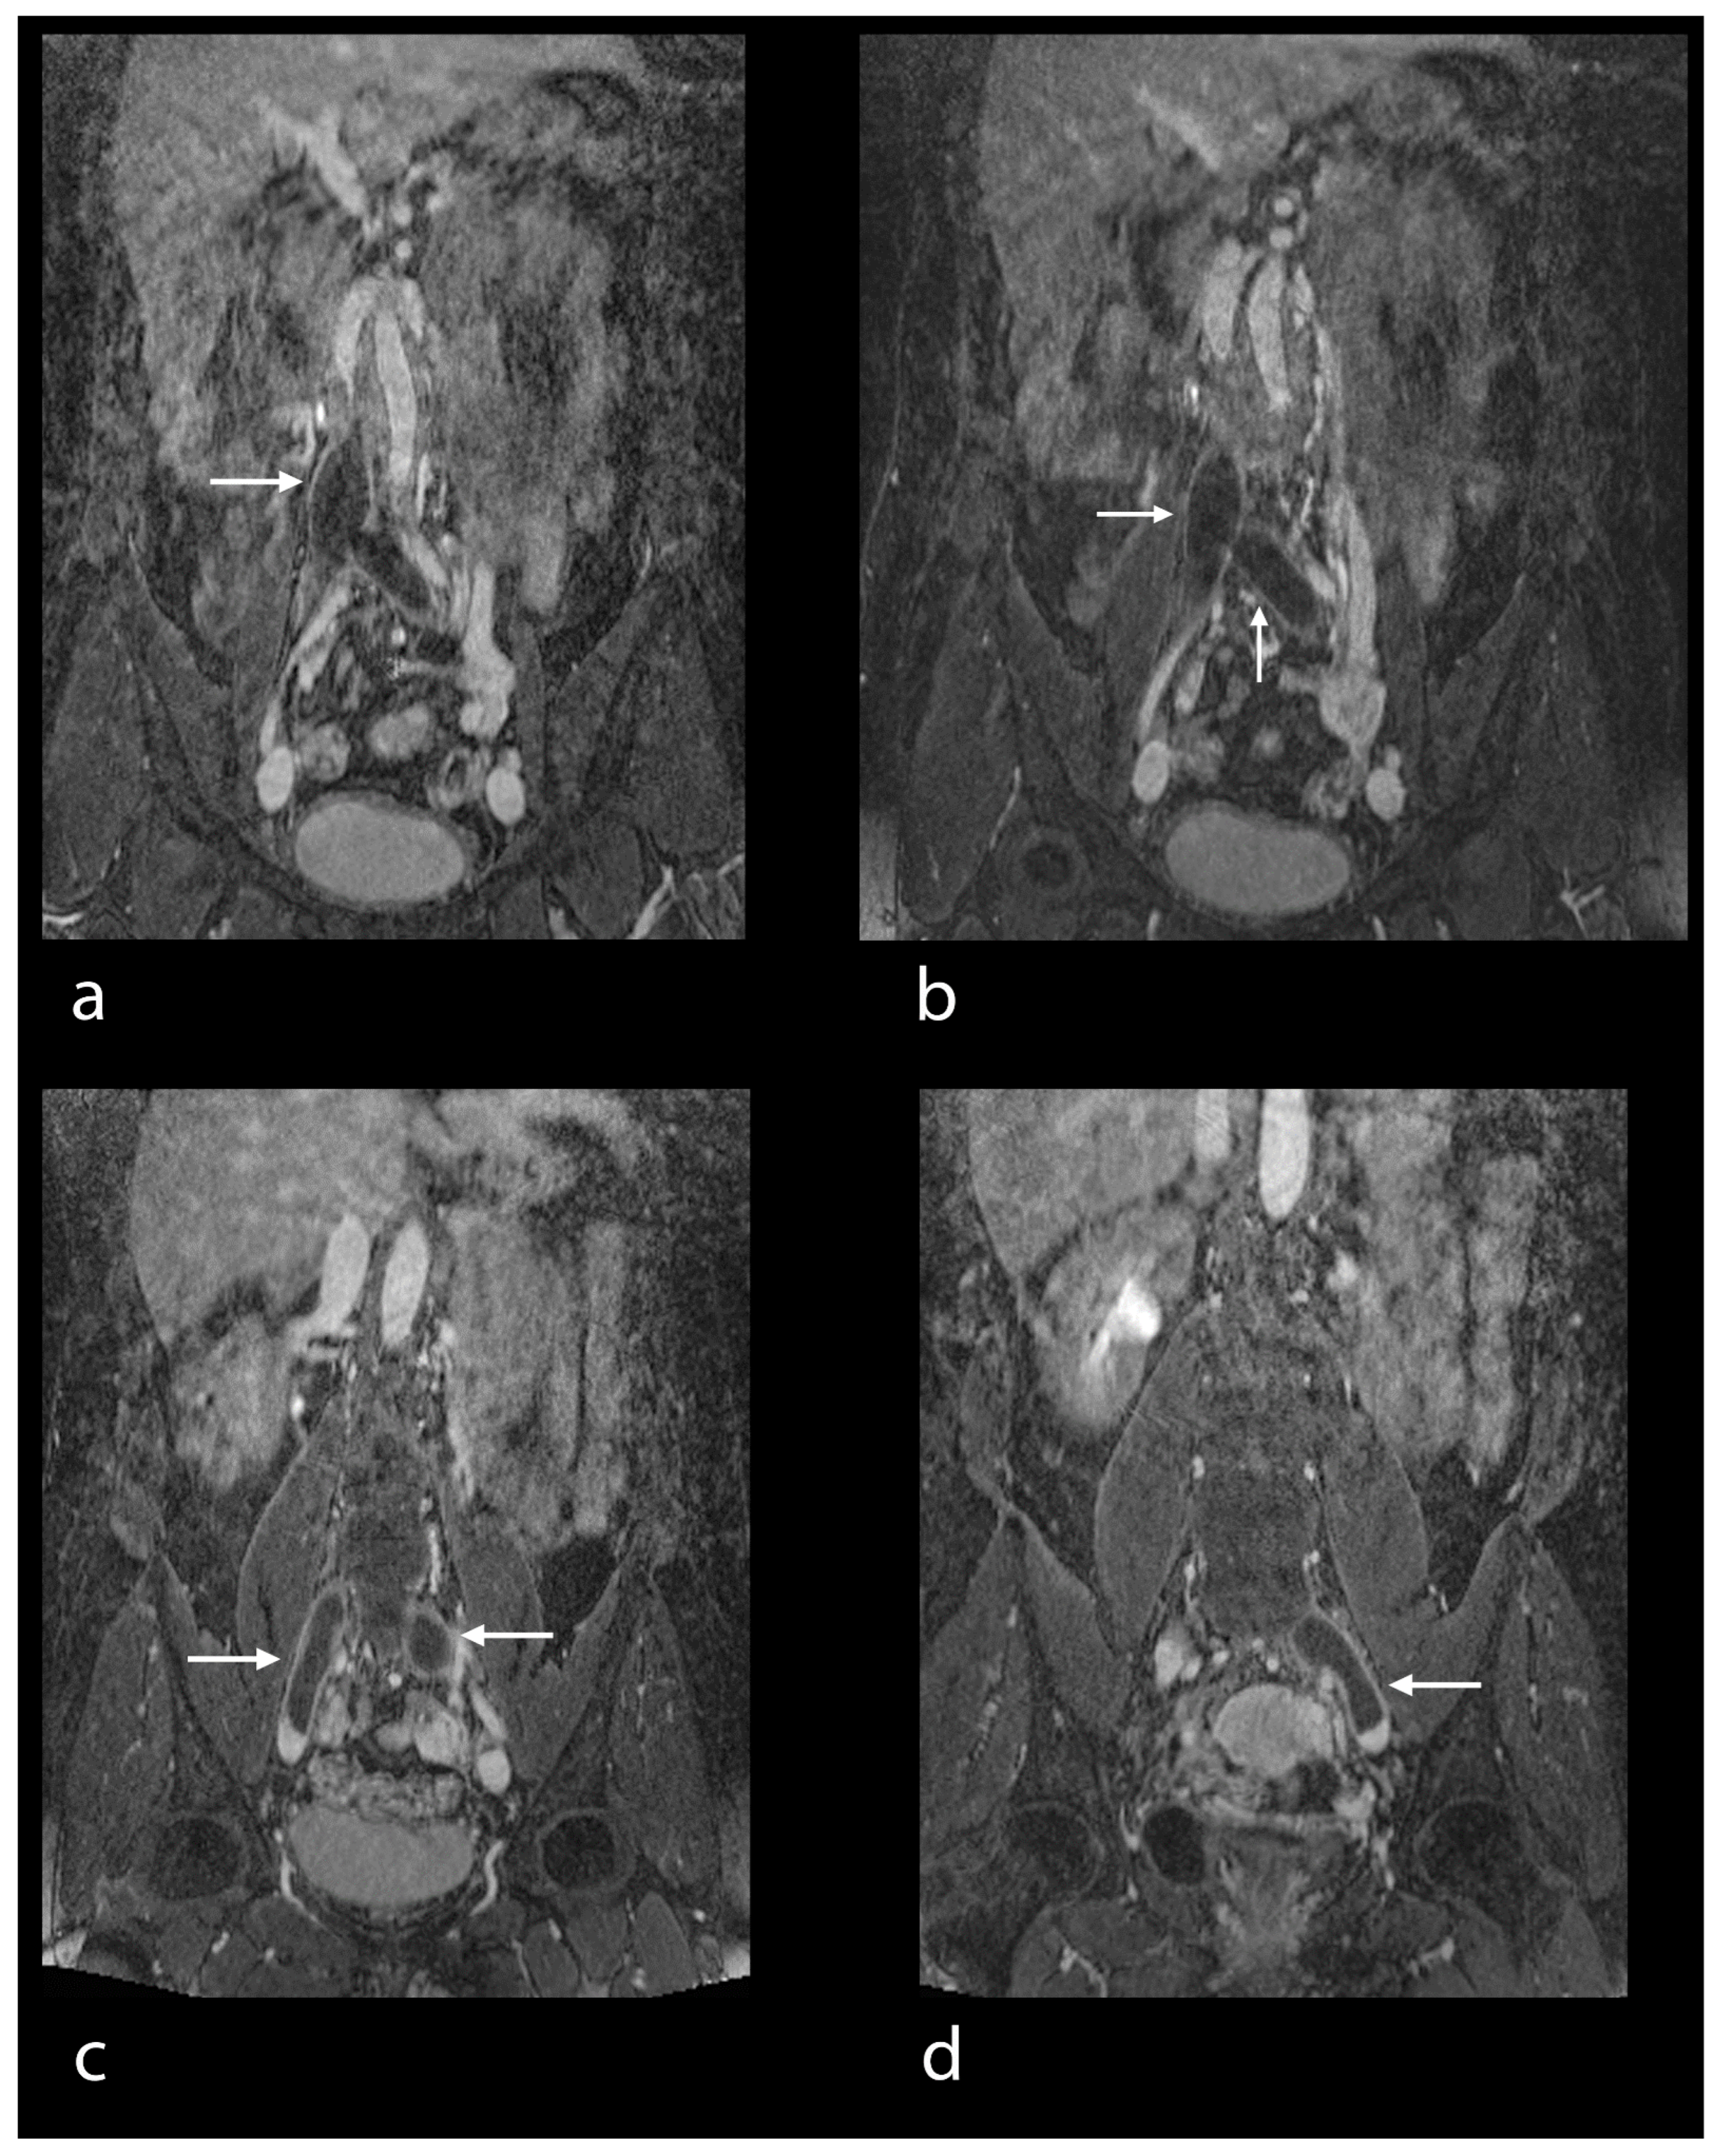

- Hansch, A.; Betge, S.; Poehlmann, G.; Neumann, S.; Baltzer, P.; Pfeil, A.; Waginger, M.; Boettcher, J.; Kaiser, W.A.; Wolf, G.; et al. Combined magnetic resonance imaging of deep venous thrombosis and pulmonary arteries after a single injection of a blood pool contrast agent. Eur. Radiol. 2011, 21, 318–325. [Google Scholar] [CrossRef]

- Aschauer, M.; Deutschmann, H.A.; Stollberger, R.; Hausegger, K.A.; Obernosterer, A.; Schöllnast, H.; Ebner, F. Value of a blood pool contrast agent in MR venography of the lower extremities and pelvis: Preliminary results in 12 patients. Magn. Reson. Med. 2003, 50, 993–1002. [Google Scholar] [CrossRef]